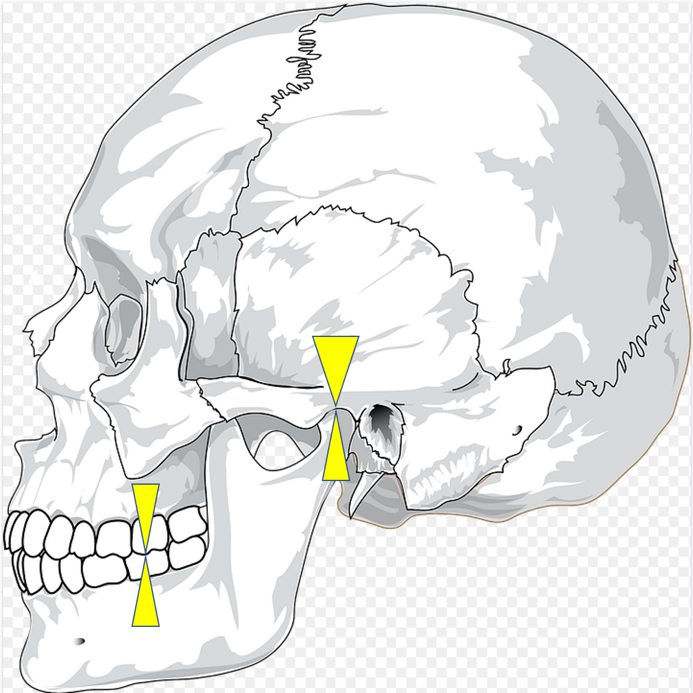

しかし、図のように、歯がかみ合ったときに、顎の関節に負担がかからない状態であれば良いのですが、

このように、歯をかみ合わせたら、顎の関節がずれてしまう人がいます。

そしてのこの方は顎の関節がラクな位置で咬むと、このようになります。顎関節はラクですが、歯の凸凹がかみ合っていないので、まともに、ものを咬めません。よって、顎に負担をかければギリギリ咬める、という状況であれば、人間は顎の関節よりも、「ちゃんと咬む」ことを優先して、食物を咀嚼してしまいます。結果、顎の関節には、負荷がかかり、人によっては顎関節症になる可能性が出てきます。

先ほど説明した、このかみ合わせの位置を中心位、といいます。